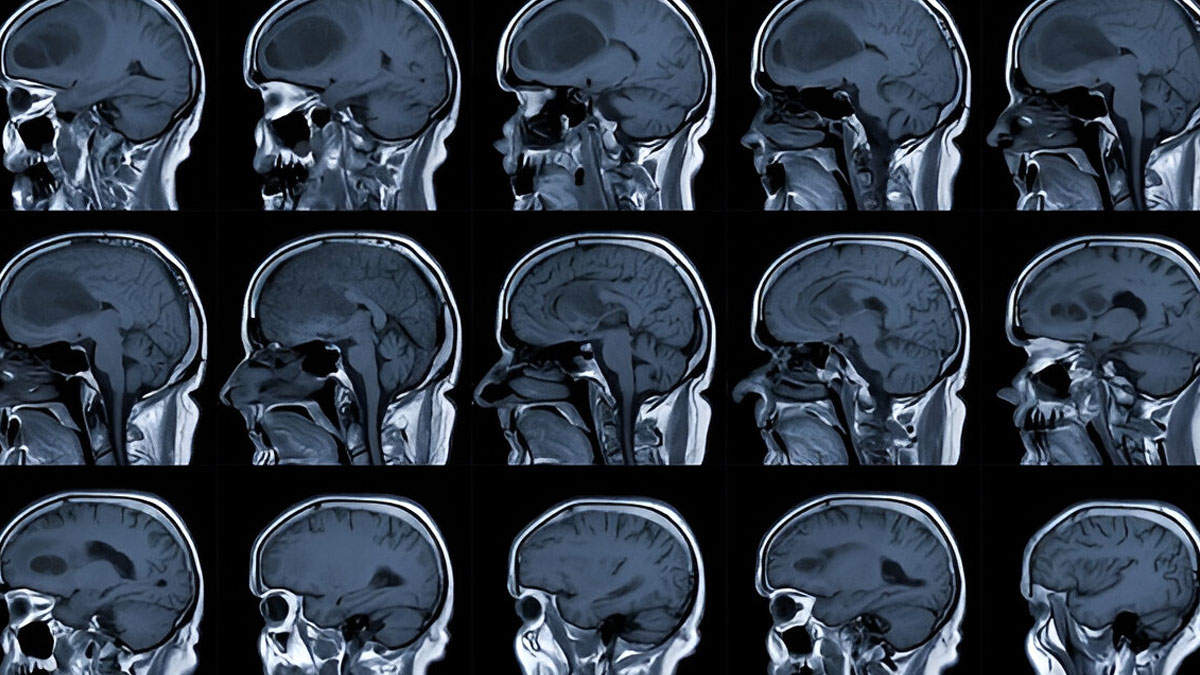

Glioblastoma, also known as glioblastoma multiforme, is the most common and aggressive type of primary brain tumour in adults. Primary brain tumours are tumours that originate in the brain, whereas secondary brain tumours spread from another part of the body.

Glioblastoma originates from glial cells, which are the supportive tissue of the brain and spinal cord.

Treatment of glioblastoma begins after a confirmed diagnosis. Tests and procedures used to diagnose glioblastoma include neurological exams, imaging tests, and a biopsy.